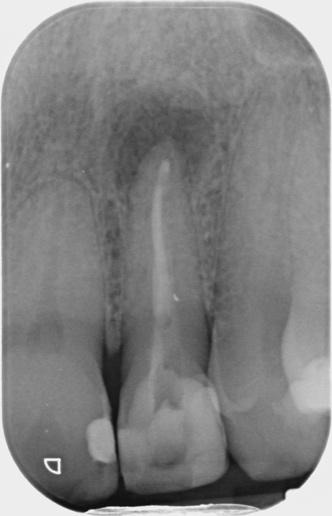

Pre-op IOPA and CBCT of the UR1 and UL2 looked like this:

Key findings from CBCT Consultant radiologist’s report by JM Radiology:

UR1

- Root filling under condensed.

- Large PARL (approx. 5mm) causing dehiscence of buccal cortex.

- Coronal one third of canal demonstrates some widening – likely to be anatomical rather than resorption and was mirrored on the UL1.

- No evidence of a fracture.

UL2

- Root filling a little under condensed.

- Large PARL; 6.5mm in diameter and dehiscence of the buccal cortex.